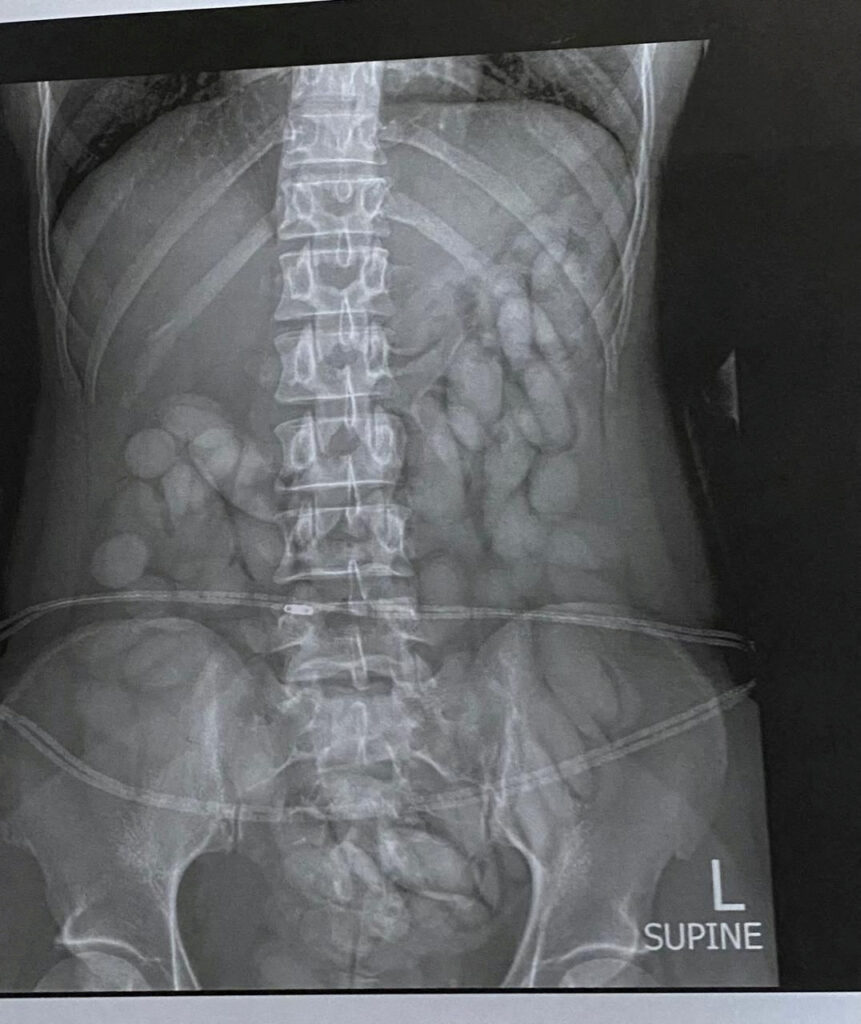

Na letališču v Južni Afriki so aretirali 30-letno državljanko Namibije. Ob opravljenem rentgenskem slikanju so v njenem trebuhu našli 68 kroglic s kokainom, ki so skupaj tehtale okoli 850 gramov.

30-letna ženska, ki so jo pridržali na letališču OR Tambo v Johannesburgu, je imela v trebuhu 68 kroglic s kokainom. Skupaj so tehtale okoli 850 gramov. Mamilo so zaznali pri rentgenskem slikanju, ki so ga opravili po aretaciji, poroča Sky News.